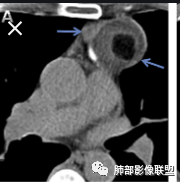

弹指之间:定位:1.非肺内来源,2.纵隔或胸膜来源;内乳动脉增粗,cor示与胸膜关系密切;

右侧内乳动脉增粗